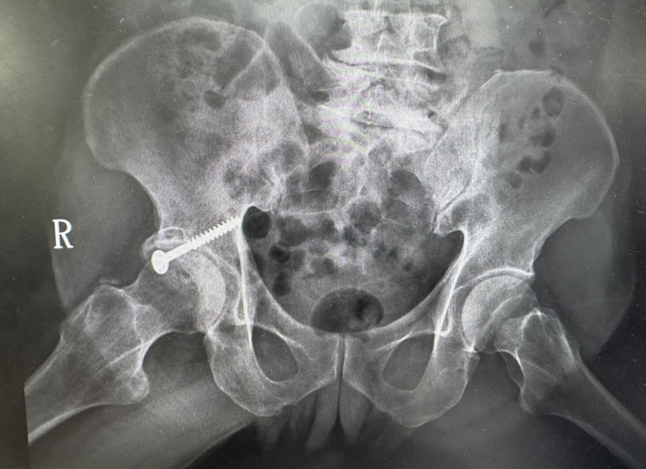

76歲男性病人多年前因髖臼骨折接受手術,術後留下垂足(foot drop)與步態異常,長期行動不便,導致外傷性退化性髖關節炎,連如廁與行走都成為挑戰。經新竹臺大分院骨科團隊詳細評估並與病人充分溝通後,決定採用「前側入路(Direct Anterior Approach, DAA)」人工髖關節置換手術,避開之前的手術區域,病人術後當天即可床邊如廁並下床行走,疼痛顯著減輕,展現微創技術在高齡手術中的安全與高效,成功改善長年困擾。

賈維焯主任說明,DAA人工髖關節置換術是近年國際間發展成熟的微創技術。新竹臺大分院骨科團隊結合術前影像分析與精準定位系統,提高手術植入穩定性與下肢長短對位準確性。與傳統後側入路手術相比,DAA術式不僅可減少術後疼痛與出血,亦能縮短復健期並降低脫臼風險。